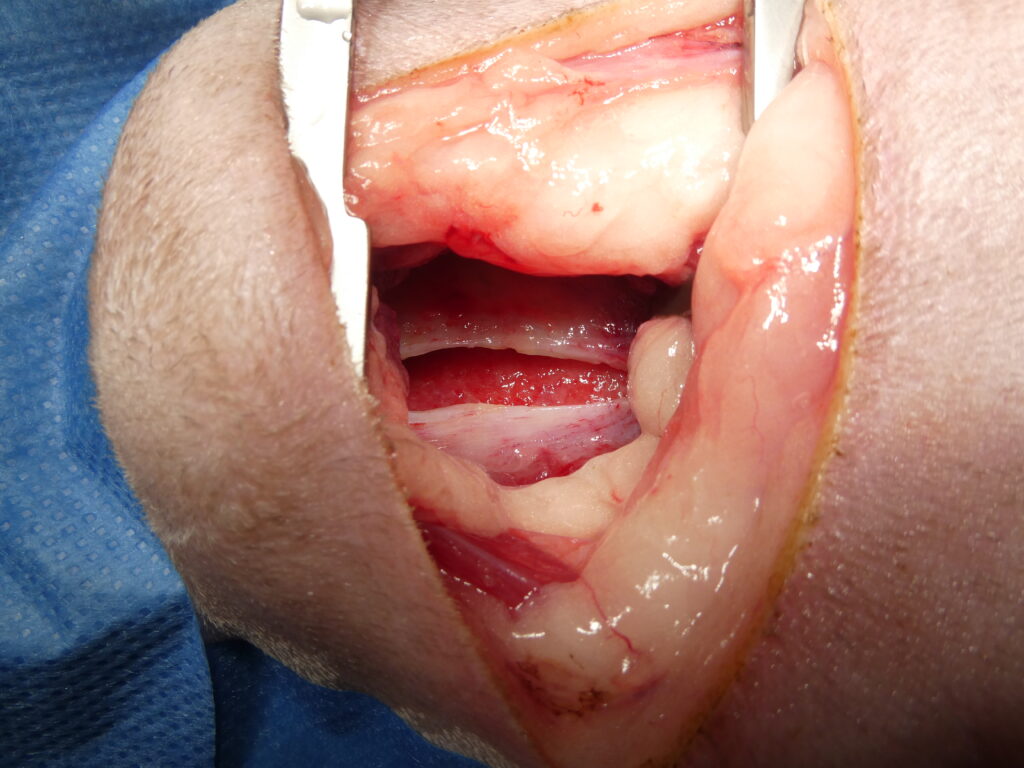

Chirurgie de persistance du canal artériel par ligature.

À gauche, ouverture du thorax par thoracotomie avec maintien de l’écartement costal à l’aide d’un écarteur de Finochietto, permettant un accès direct et sécurisé au médiastin.

Au centre, dissection minutieuse des structures vasculaires et passage d’un fil de suture à l’aide d’un clamp spécifique en arrière du canal artériel persistant, en vue de réaliser une double ligature.

À droite, canal artériel complètement ligaturé par deux nœuds successifs, interrompant la communication anormale entre l’aorte, située au-dessus de la ligature, et le tronc pulmonaire, situé en dessous, avec un résultat immédiat et durable lorsque la ligature est complète.